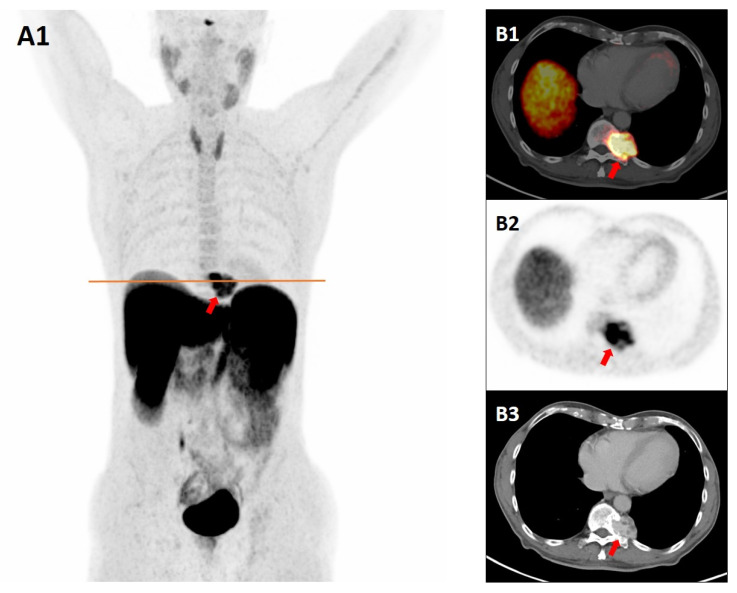

We report the case of a 77-year-old male with a paraspinal mass at the Th11 level. Given its morphology and location, CT and MRI findings raised the suspicion of paraganglioma. A somatostatin receptor positron emission tomography/contrast-enhanced-CT (SSTR-PET/CE-CT) scan with Gallium-68 DOTATATE, performed for staging of suspected paraganglioma, demonstrated intense tracer uptake in the lesion, reinforcing the suspicion of a neuroendocrine tumor with increased SSTR expression. However, histopathology demonstrated a cavernous hemangioma with partial sclerosis, and immunohistochemistry showed strong endothelial SSTR expression. This case highlights the possibility of false-positive findings on SSTR PET/CT, as a cavernous hemangioma may closely mimic paraspinal paraganglioma in both imaging appearance and tracer uptake pattern. Notably, the intense tracer accumulation in this case was not solely related to the lesion's hypervascularity but predominantly to the marked endothelial overexpression of SSTR demonstrated on immunohistochemistry.